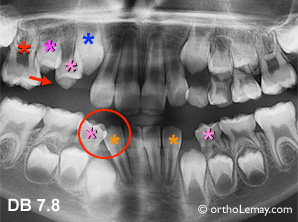

Cas DB : Ce jeune patient (7.8 ans) a perdu la deuxième molaire temporaire supérieure droite prématurément car la molaire permanente a fait éruption sous la molaire temporaire et l’a fait tomber. Il en résulte une perte d’espace (flèche) qui empêchera l’éruption de la deuxième prémolaire qui doit remplacer la dent tombée. Il serait indiqué de soit récupérer l’espace perdu ou au moins d’utiliser un mainteneur d’espace pour éviter une perte additionnelle d’espace et empirer les problèmes d’éruption dans ce quadrant.

À l’arcade inférieure, suite à la perte de la canine temporaire droite bien avant la perte de celle du côté opposé, les incisives ont migré vers la droite et la latérale permanente est en contact avec la première molaire temporaire inférieure droite bloquant complètement l’éruption éventuelle de la canine.

Cas DB

Cas DB : (A) Les incisives permanentes sont beaucoup plus larges que les temporaires alors il faut s’attendre à un manque d’espace pour accommoder les dents car la croissance n’aidera pas ce problème. À l’arcade inférieure (C), l’incisive centrale permanente droite sort derrière 2 incisives temporaires. Des extractions sélectives peuvent être éventuellement indiquées pour donner l’espace aux centrales inférieures. Dans certains cas, une fois ces extractions faites, la langue peut pousser les dents vers l’avant et améliorer la situation. Il faut cependant comprendre que malgré l’extraction de dents de lait (temporaires) le manque d’espace persiste. (Voir la légende pour identifier les dents)